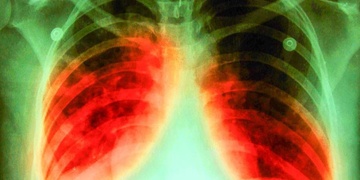

Ubytovny a montovny - hrozba TBC

20. března 2019 21:42 , aktualizace 23:17

Plzeňsko se dostalo na první místo v ČR v počtu cizinců nakažených tuberkulózou!